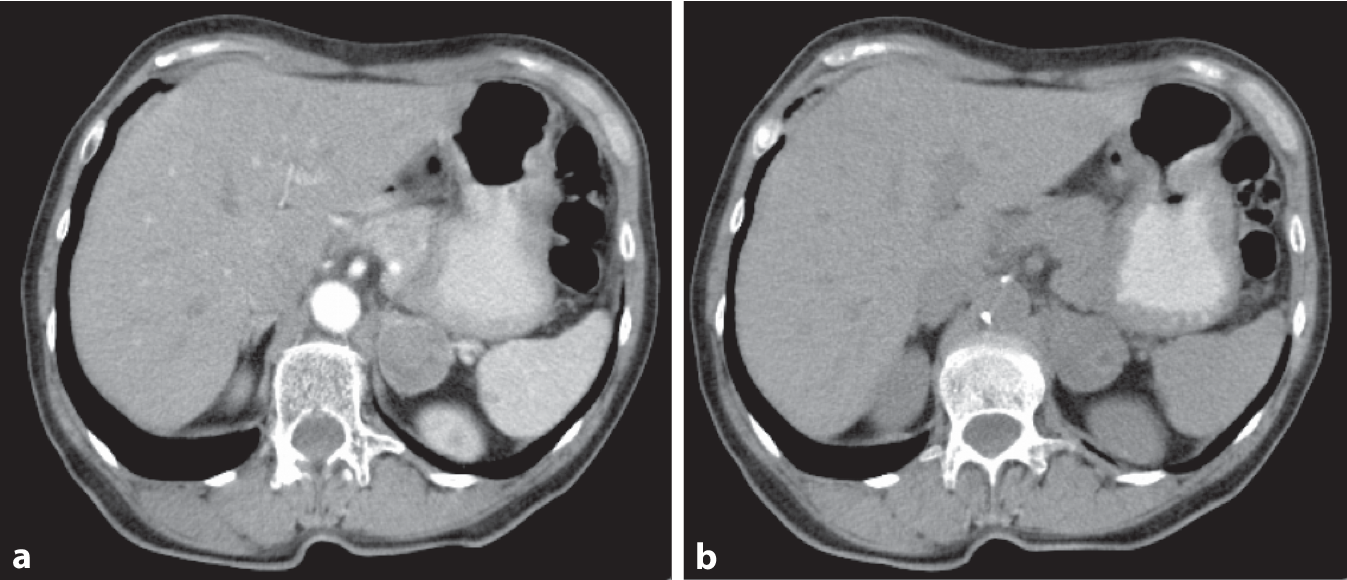

Bildgebung

Abb. 3

Computertomographie eines Phäochromozytoms links (a arterielle KM-Phase, b nativ)